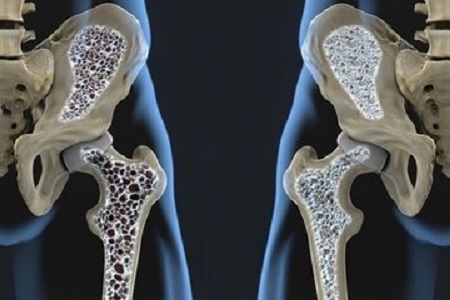

بهترین پیشگیری از پوکی استخوان مشخص شد

پوکی استخوان در زنان بیشتر از مردان است، افرادی که زمینه خانوادگی دارند امکان ابتلا به این بیماری در آنها بیشتر است. تشخیص این بیماری از طریق اسکن سنجش تراکم استخوان امکانپذیر است.